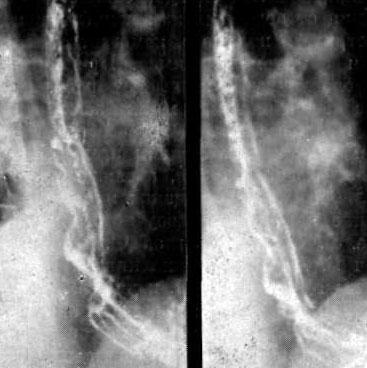

Современные технологии в медицине: рентгенодиагностика заболеваний желудка